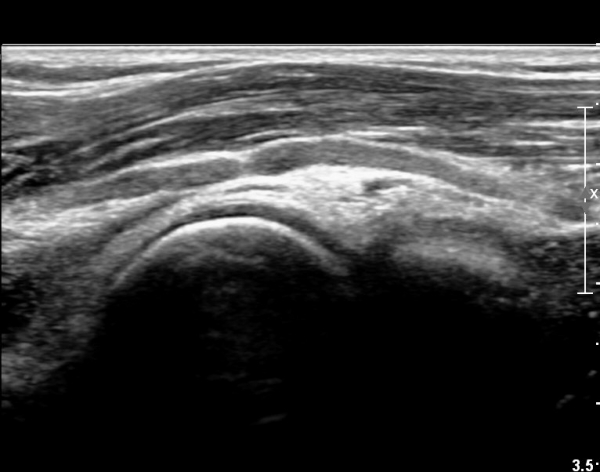

ÆÈ²ÞÄ¡ ¾Õ, Èİñ°£½Å°æ Ⱦ´Ü¸é °Ë»ç¿¡¼ Èİñ°£½Å°æÀÇ ºÎÁ¾ÀÌ °üÂûµÇ°í (»çÁø 1),